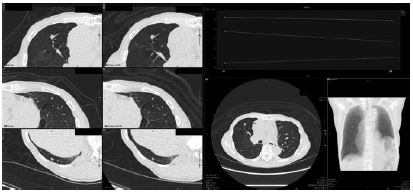

さらにクリックしてフォローアップ対象にすると、次から勝手にフォローアップしてくれる。フォローアップビューでは、対象の結節をピックアップし、経時的なサイズ変化がグラフに表示される(図3)。サイズも自動計測してくれるので客観性がある(計測方法は細かく設定変更できる)。このケースではフォローアップ期間が短いので変化は乏しいが、今後、長い経過をみるときにとても便利である。